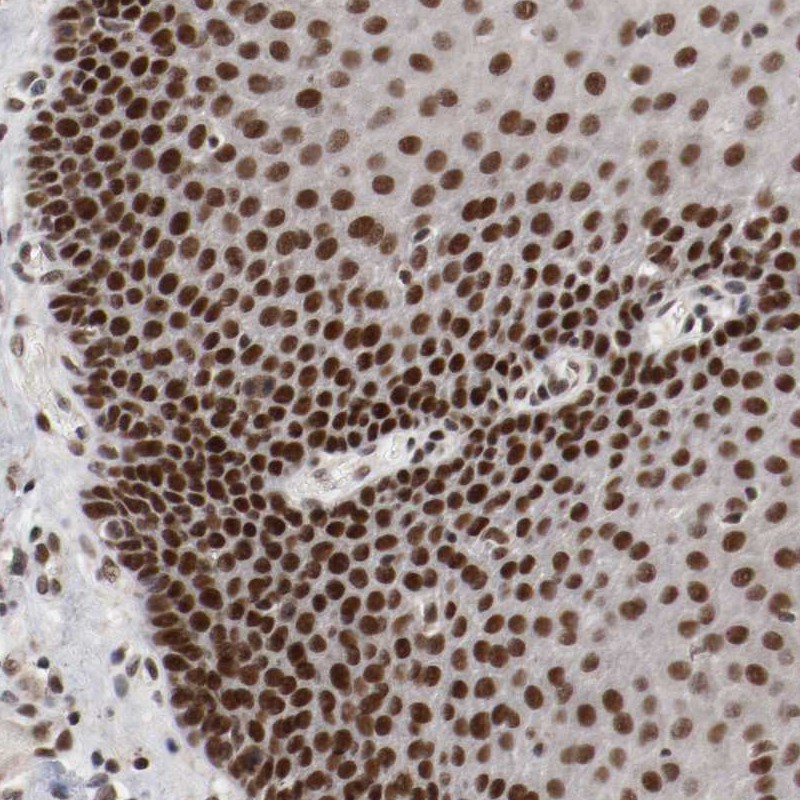

Immunohistochemical staining of human esophagus shows strong nuclear positivity in squamous epithelial cells.